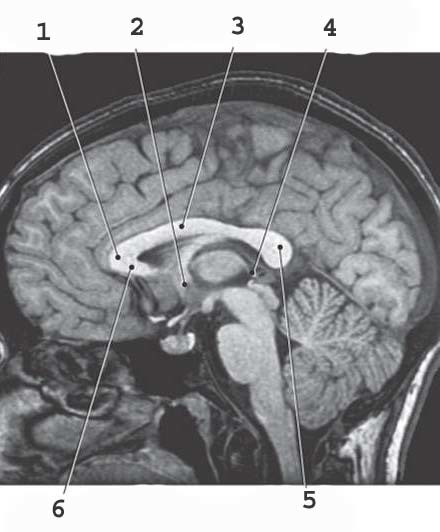

1

Lateral Vetnricle

2

4th ventricle

corpus collosum genu

3

septum pellucidum

4

3rd ventricle

5

corpus collosum splenium

6

corpus collosum rostrum